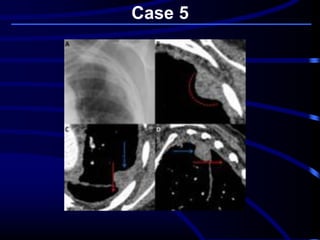

Case 5

A 68-year-old asymptomatic

nonsmoking woman underwent

preoperative screening chest

radiography in preparation for a total

knee arthroplasty. The radiographic

findings prompted subsequent chest

CT

Where is this lesion MOST

LIKELY located?

A. Lung parenchyma.

B. Mediastinum.

C. Pleura.

D. Chest wall..

What is the MOST LIKELY

diagnosis?

A. Primary lung cancer.

B. Chest wall chondrosarcoma.

C. Pseudotumor or vanishing

tumor of the pleura.

D. Localized fibrous tumor of the

pleura..

..pleura